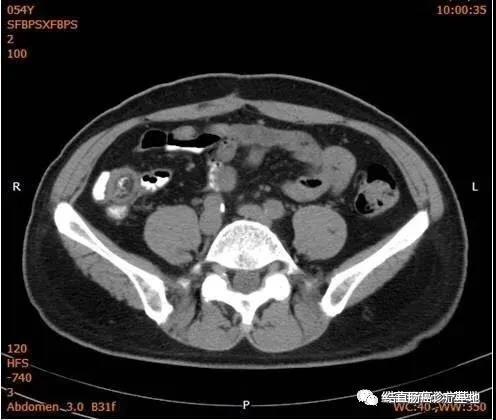

2017年9月18日评效:ECOG1;CEA 2.60ng/mI,CA19-9 9.92U/mI。胸部CT、全腹部+盆腔CT未见明显异常(下腹部CT图片)